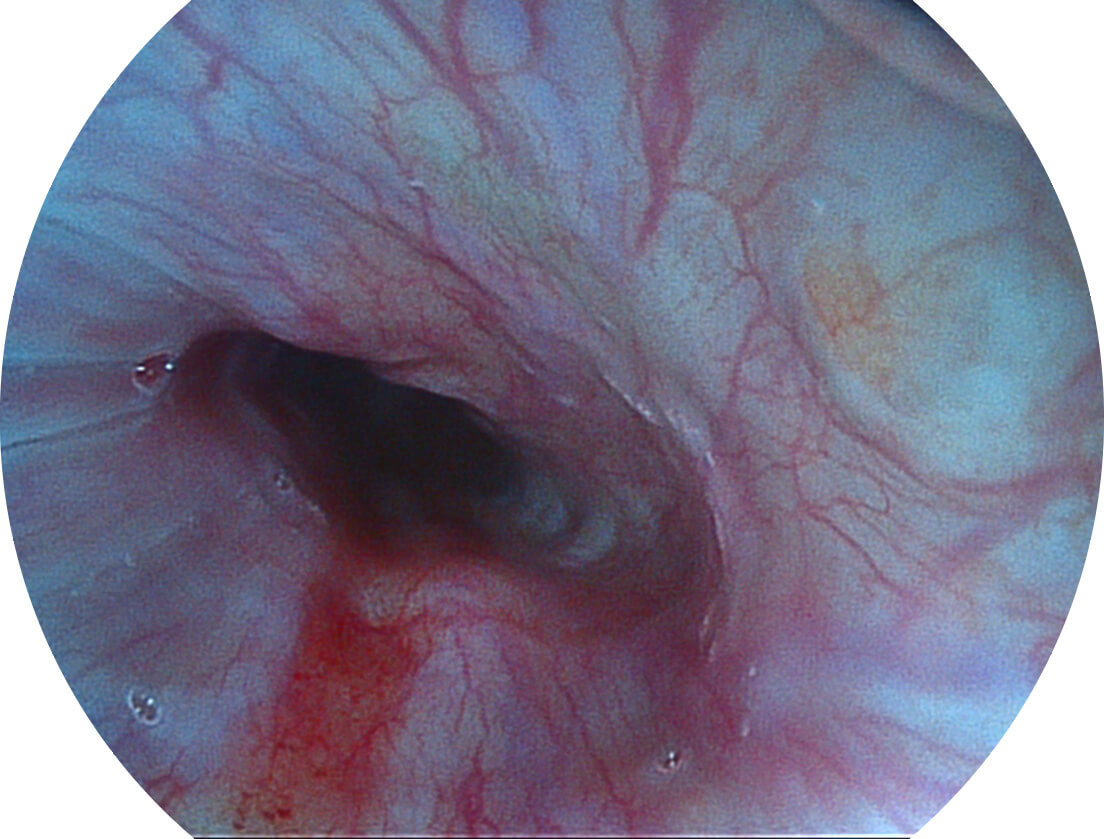

光电复合染色成像技术

Versatile Intelligent Staining Technology, VIST

强调浅层黏膜结构的同时,保证照明亮度和提升浅层微血管与中层血管颜色对比度,病变边界更清晰。

• 白光图像 VIST图像